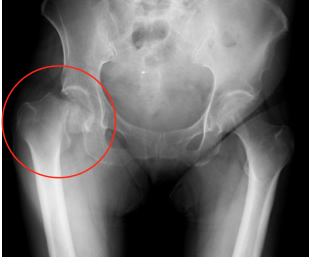

また70歳以下や比較的活動性の高い方には前記のような人工骨頭置換術ではなく全人工関節置換術(図3)を主に前方アプローチ(DAA)で行っています。全人工股関節置換術後の多くの方は退院まで一貫して当院でリハビリを行っており受傷以前の生活にかなり近づけることができています。

図3-1

大腿骨頸部骨折 人工股関節置換術前

図3-2

全人工股関節置換術後

図3-1

大腿骨頸部骨折 人工股関節置換術前

図3-2

全人工股関節置換術後

骨折箇所に人工骨を置換します。図3-2のレントゲンで白く写っているのは人工骨です。